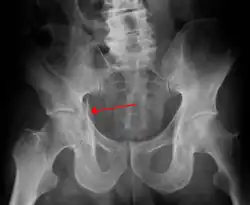

High anterior column fracture 3 D CT scan picture -

High anterior column fracture after fixation with screws and plates